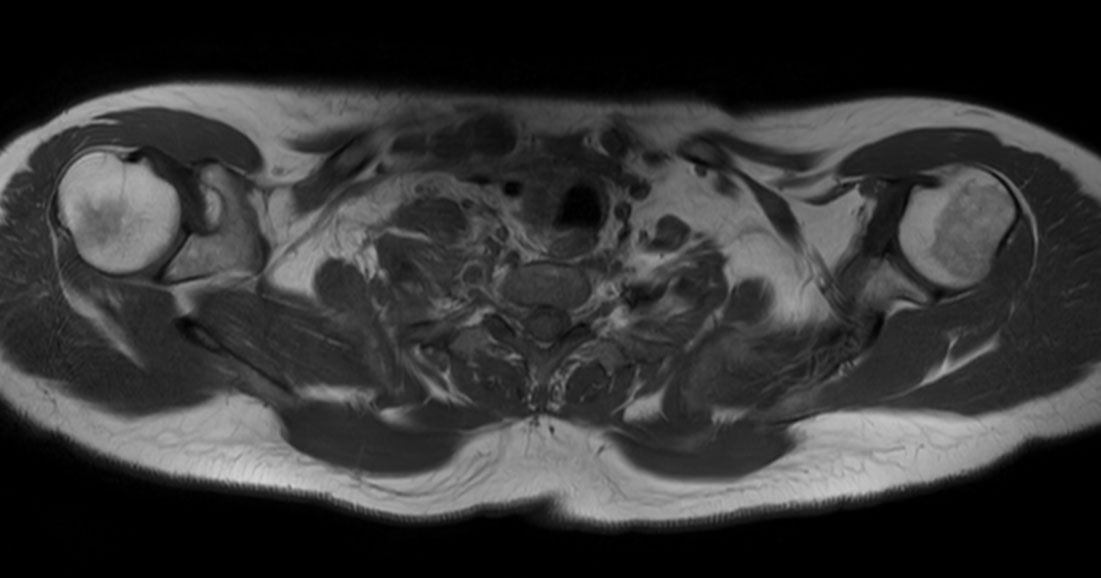

Axial T2w mDIXON XD TSE (In Phase)